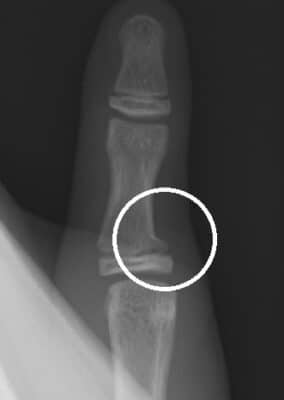

牛久市で指の怪我(突き指・骨折・脱臼)にお悩みの方へ:症状の見分け方から…

骨折・脱臼

さわやか千葉県民プラザ(指骨骨折)

さわやか千葉県民プラザ(指の脱臼)

春日部市市民活動センター(指の脱臼)